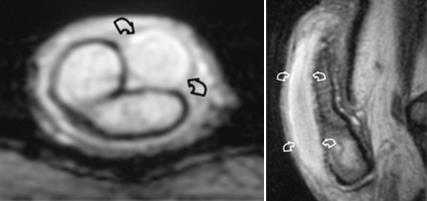

Липома семенного канатика, гидроцеле

Гематома правого семенного канатика после впарвления паховой грыжи.

Варикоцеле (стрелка) и гидроцеле (*) слева.